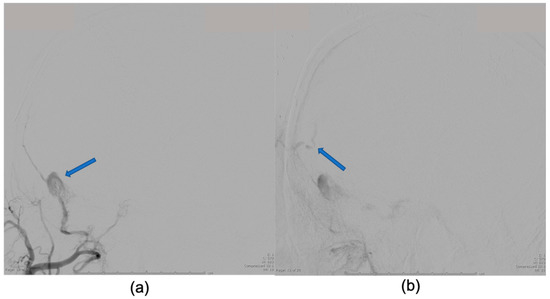

2. Case Presentation